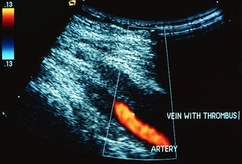

DVT Warning Signs

As many as 900,000 Americans a year get this type of blood clot, and up to 100,000 die because of it. Here's what to watch for.